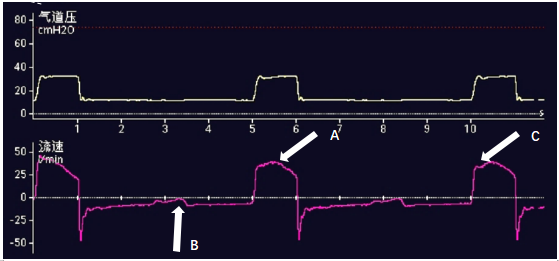

(2)根据通气开始瞬间的气道压力和流量变化来判断。此种方法基于吸气触发灵敏度的原理,在绝大多数患者中准确性较高,而且也能判断某些常见的非自主节律问题。压力触发灵敏度的原理是当呼吸机在呼气相监测到气道压力的下降值达到预设的压力触发灵敏度时启动送气过程,我们可以在呼吸周期启动的时间点看到有较明显的气道压力下降(图2-A),可以判断该次送气通常是由患者主动吸气触发。当采用流量触发灵敏度时,我们也能在流量时间波形上看到有流量上升的拐点,该拐点对应的流量大小即预设的流量触发灵敏度(图2-C)。使用流量触发灵敏度时,通常要求呼吸机在呼气相输送一较低流量的基础气流,可以用于克服呼吸环路的阻力;而压力触发时,呼吸环路的死腔需要患者自己克服。因此流量触发灵敏度的同步性能通常优于压力触发,常作为首选触发方式。当然,压力的下降和流量的上升在流量触发时通常是同步的;但在压力触发方式下,触发之前一般见不到流量的上升。

图2 根据波形判断是否存在自主呼吸